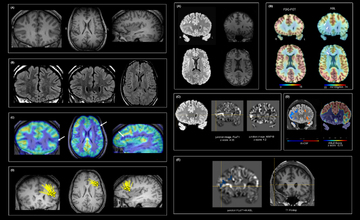

At UT Southwestern, epilepsy research spans the full translational spectrum—from basic scientists investigating disease mechanisms in model systems to clinical investigators leading outcomes and patient-centered studies. Our work addresses epilepsy across the lifespan, including pediatric and childhood disorders, adult epilepsy, and conditions affecting older adults. Research efforts are further strengthened by international collaborations and by growing interests in artificial intelligence, machine learning, and natural language processing to advance quality improvement, medical education, and the delivery of high-quality care to underserved populations.